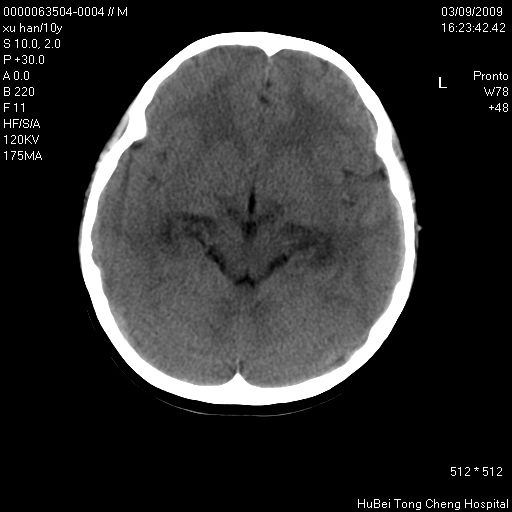

以下是引用道哥在2009-3-9 18:40:00的发言:[br]未见明显异常,必要时mr(dwi)成像。

以下是引用余辉在2009-3-10 11:01:00的发言:[br]考虑双侧海马急性缺氧性损伤